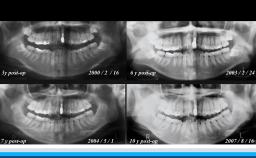

高齢者の咬合力回復は,栄養摂取や全身の筋力維持に貢献できる.インプラント治療もQOL向上に大きく寄与できる可能性を有する.一方,術後の全身の健康状態の変化に対応したメンテナンスを術前から考える必要がある.